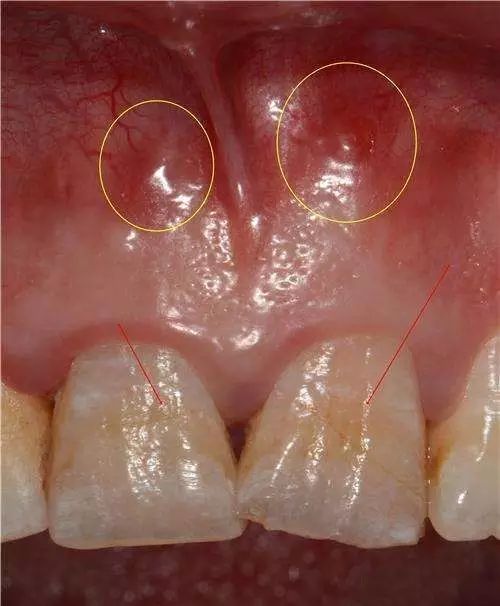

手用扩大针作根管清理或扩大,较少出现侧穿现象,除非是用大号扩大针作强行扩大。采用机用扩大针或桩冠修复时进行钉道制备,如操作不慎较易侧穿。侧穿后如未发现或处置不当,日后可出现有窦道的慢性根尖周炎。

牙齿的根管系统比较复杂,采用常规方法治疗,对根管形态变异及侧付根管中感染物质难以彻底清除,这些感染物质日后将成为细菌生长繁殖的场所。如Vertucci分类Ⅲ、Ⅴ、Ⅶ型根管都仅有一个根管口,常规方法很难将分歧以下根管中的牙髓或腐质全部清除,日后就有可能成为治疗失败的原因。过度弯曲畸形或有髓石、异物阻塞的根管,都会给治疗带来较大的难度,也会使治疗效果受到一定的影响。此外,除上前牙外,其余牙齿的根管数目变异较大,在无法直视的开髓洞,有时也难免会遗漏变异的根管,这也是导致治疗失败的一个重要原因。根管内因素治疗失败,查清原因后重新治疗,大都可以治愈。根管外因素所致失败,除部分病例配合外科可以治愈,大多数病例重新作根管治疗也难以成功,形成真正的难治性根尖周炎。笔者在《实用牙髓病诊疗学》中将窦道口形状分为6种,其中的脓性针眼状窦口(压有白色脓液溢出,窦口仅有针眼大小无突起)几乎都是根管外原因,单纯根管治疗难以奏效。